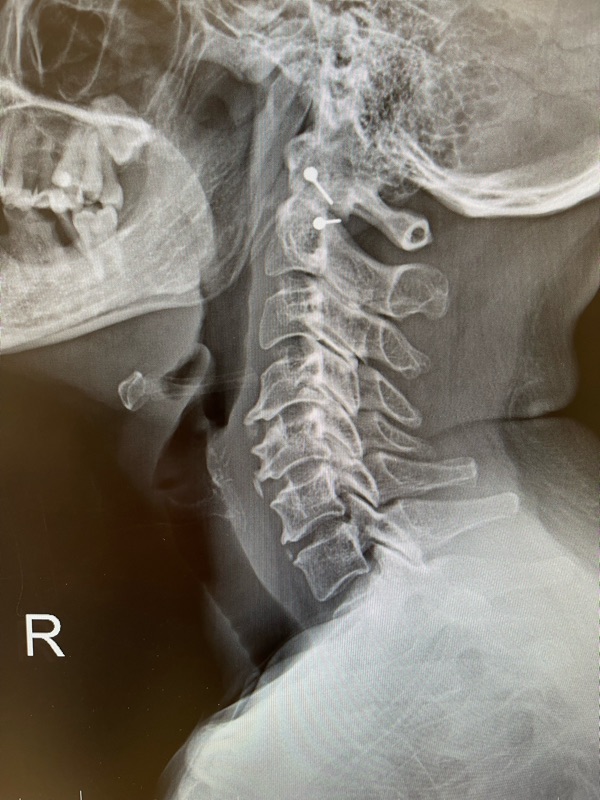

✔ ถ่ายภาพเอกซเรย์กระดูกต้นคอ

ความจริงคือ… อาการปวดคอส่วนใหญ่ไม่ได้มาจากหมอนรองคอเสื่อมเพียงอย่างเดียว แต่เกิดจากกล้ามเนื้อ ข้อต่อคอ และเส้นประสาทรอบคอร่วมด้วย ซึ่งทำให้ปวดเรื้อรังแม้ภาพเอกซเรย์จะดูไม่รุนแรง

👉 ดังนั้นอาการปวดคอไม่ได้ขึ้นกับภาพเอกซเรย์เสมอไป แต่ขึ้นกับการทำงานของโครงสร้างรอบคอทั้งหมด

แม้เอกซเรย์จะบอกว่า หมอนรองคอเสื่อมไม่มาก แต่ปวดเรื้อรังได้ เพราะเกิดจากกล้ามเนื้อ–ข้อต่อคอ–เส้นประสาทร่วมกัน